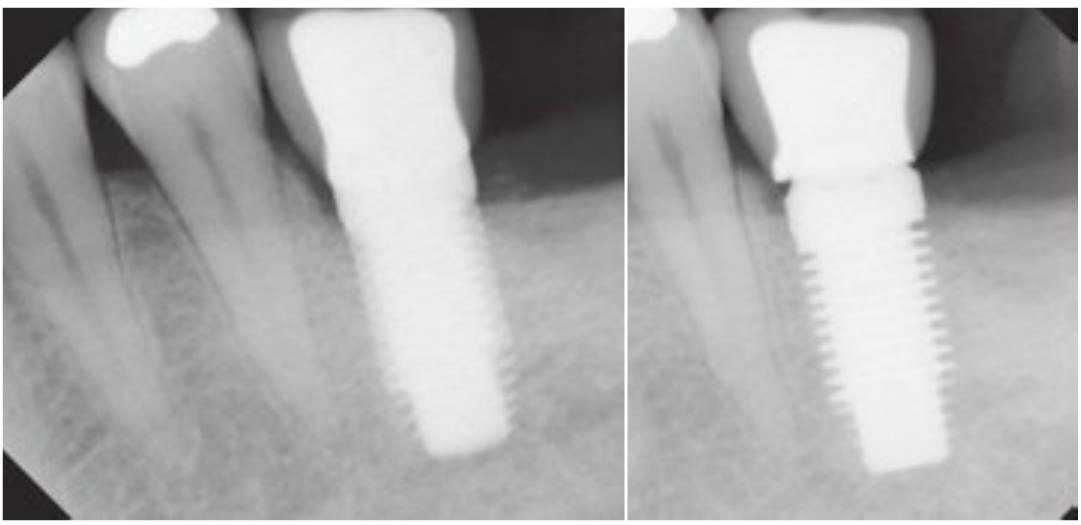

Imágenes del pilar dental y del componente protésico

En el momento de hacer una evaluación para la transferencia de impresiones junto con la colocación del componente del pilar de dos piezas, se deberían tomar radiografías para verificar que la adaptación sea segura. Se deberían emplear radiografías intraorales debido a su alta resolución geométrica para evaluar cualquier discrepancia de ajuste.

En cualquier caso, se debe de tomar la precaución de que el haz de rayos X sea dirigido hacia un ángulo correcto del eje longitudinal del implante. Incluso una leve angulación permitiría que no se detectara un pequeño espacio. Cuando el posicionamiento para las radiografías periapicales es difícil, se pueden emplear radiografías de aletas de mordida o panorámicas (figs. 3-25 y 3-26).